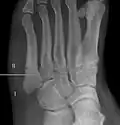

Jones fracture as seen on Xray

A Jones fracture is a broken bone in a specific part of the fifth metatarsal of the foot between the base and middle part .[8] In general, fifth metatarsal fractures heal readily, but a Jones fracture must be recognized and accurately diagnosed because of its higher rate of delayed healing or nonunion.[4] It results in pain near the midportion of the foot on the outside.[2] There may also be bruising and difficulty walking.[3] Onset is generally sudden.[4]

The fracture typically occurs when the toes are pointed and the foot bends inwards.[6][2] This movement may occur when changing direction while the heel is off the ground such in dancing, tennis, or basketball.[9][10] Diagnosis is generally suspected based on symptoms and confirmed with X-rays.[3]

Diagnostic X-rays include anteroposterior, oblique, and lateral views and should be made with the foot in full flexion.